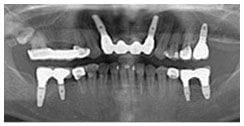

X 光片

術後X光片